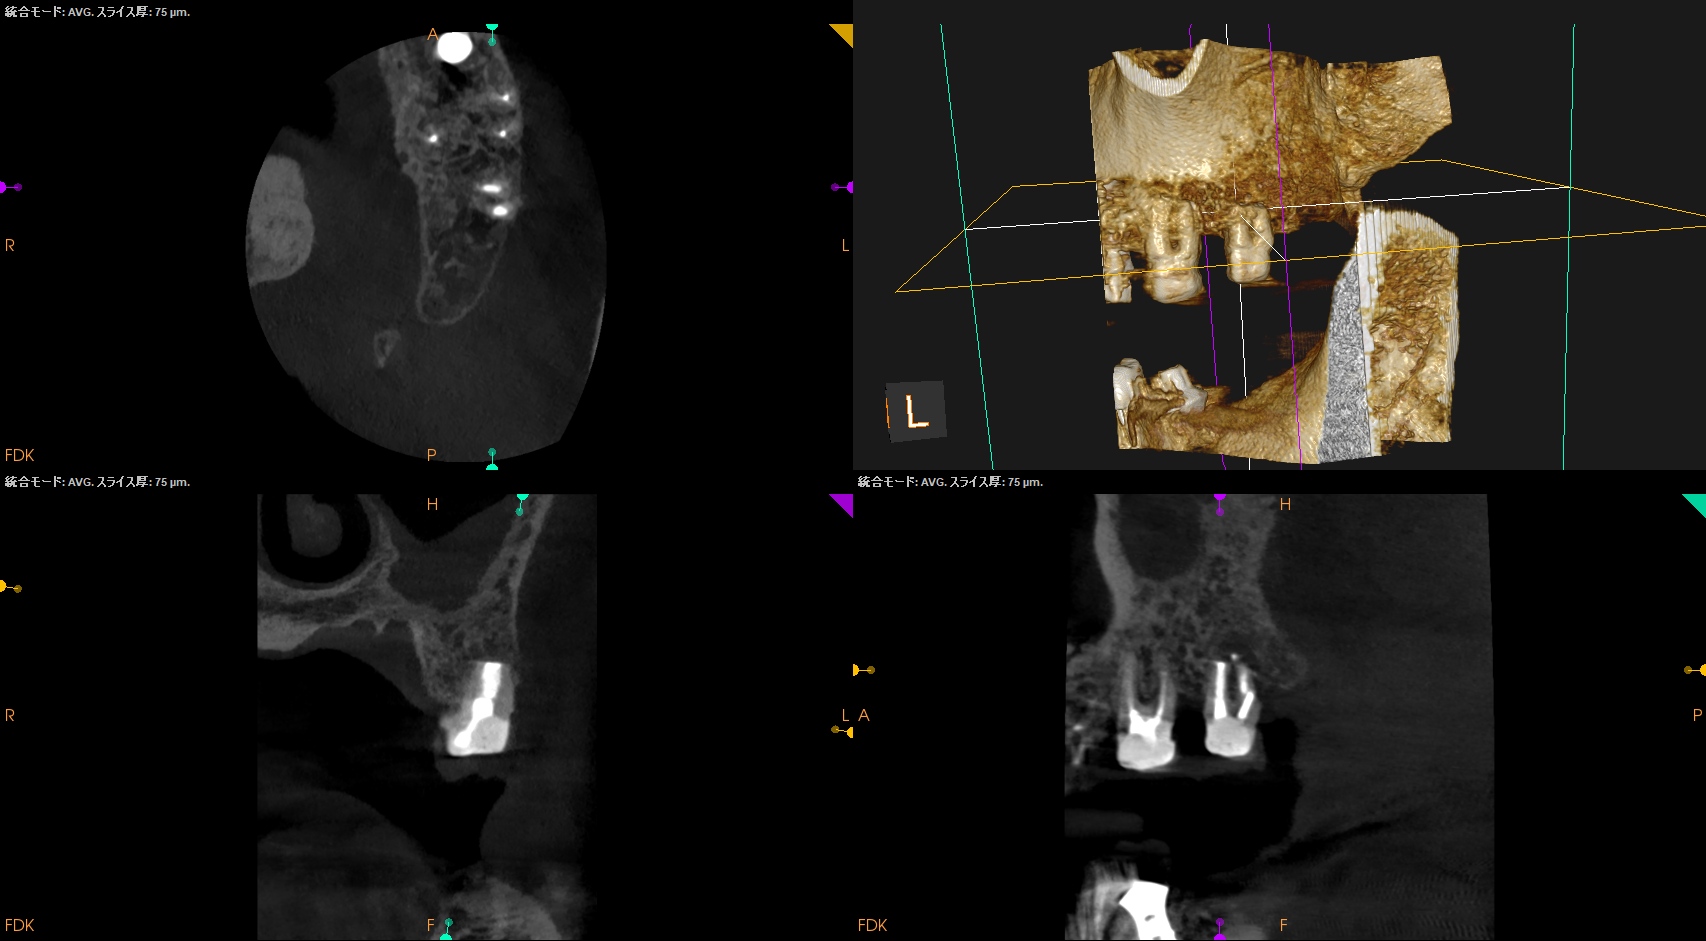

#15 Intentional Replantation 6M recall(2025.10.8)

術前の臨床症状は喪失した。

術直後と比較した。

歯槽骨がだいぶ回復している。